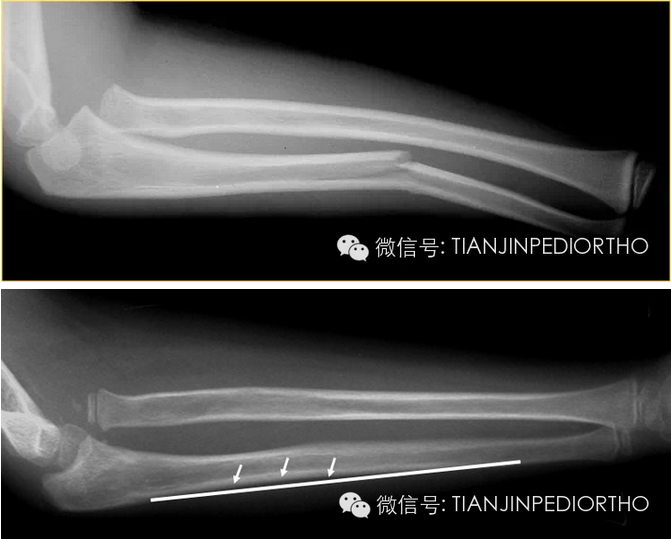

小儿孟氏骨折图片,孟氏骨折图片

小儿孟氏骨折,千万别遗漏了桡骨头脱位